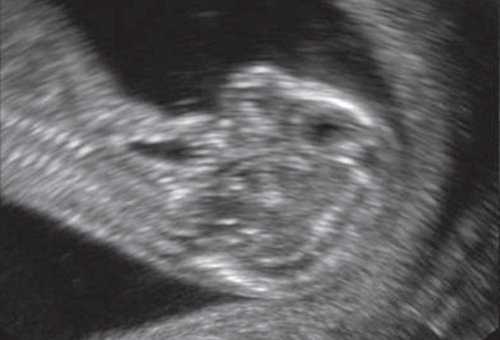

Рис. 1. Профиль плода с синдромом агнатии-голопрозэнцефалии в 12 нед беременности.

Рис. 2. Фенотип лица плода при синдроме агнатииголопрозэнцефалии в 12 нед беременности.